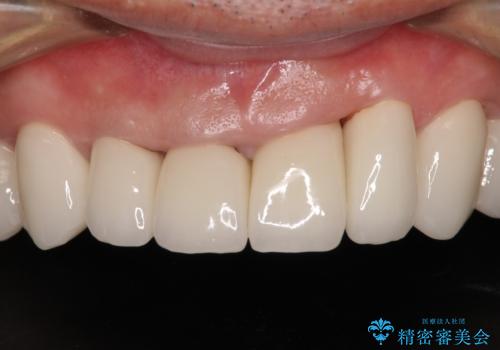

変色した前歯をきれいにしたい 部分矯正を併用した前歯の審美歯科治療

- 幼少期の薬剤の影響で歯が変色していていることを気にして来院された患者様です。

仕事も落ち着き、長年気にしていた前歯の色をきれいにしたいとのことでした。

上下ともに前歯のセラミッククラウンによる補綴治療を希望されていましたが、下顎前歯は叢生が強いため、補綴治療前に部分矯正を行って歯列を整えた上で、補綴治療を行うこととしました。